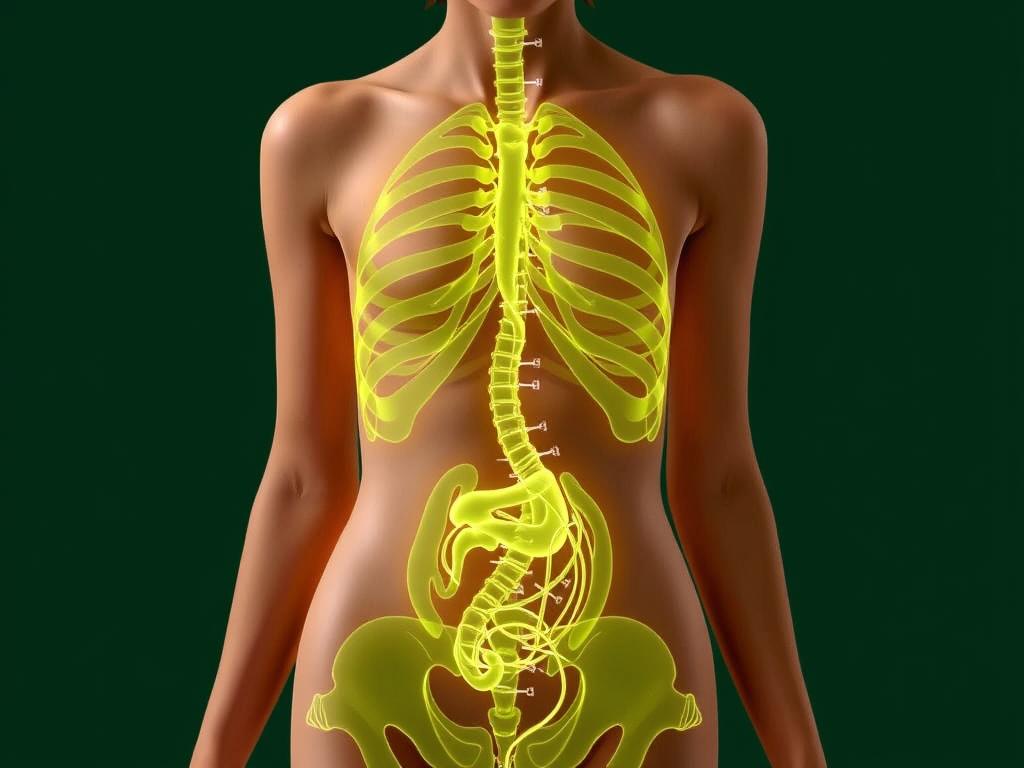

Робот Да Винчи позволяет проводить различные операции в разных областях медицины. Некоторые из них включают:

- Хирургия пищевода и желудка. Робот позволяет удалить опухоли или провести реконструкцию пищевода и желудка.

- Процедуры на гинекологическом поле. Робот Да Винчи может быть использован для удаления фиброидов матки или для проведения гистерэктомии.

- Урологические операции. Робот позволяет проводить робот-ассистированную радикальную простатэктомию или нефрэктомию.